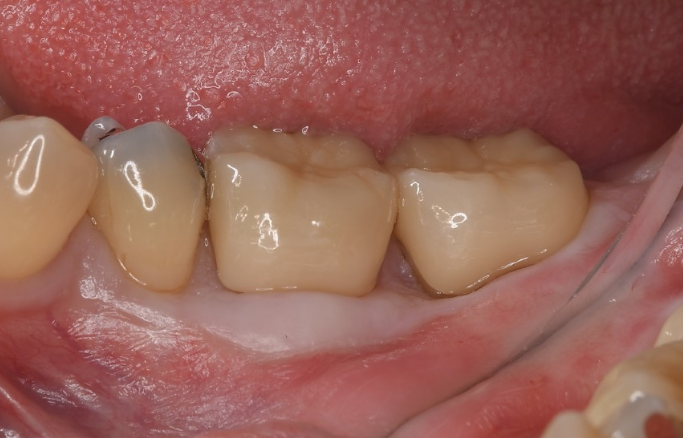

症例3

| 項目 | 詳細 |

|---|---|

| 患者様データ | 40代 女性 |

| 来院時の主訴 | 「歯がグラグラする。」 |

| 医院の診断 | 重度の歯周病、夜間歯ぎしり習慣 |

| 通院期間 |

1年 |

| 来院回数 | 8回 |

| 治療費 | 総額:220,000円(税抜) 【内訳】 歯周組織再生療法220,000円(費用は範囲によって異なります。) |

| リスクと副作用 | メインテナンスが必要、正しい歯磨き習慣が必要不可欠 |

| ここがこだわりのポイント!☝ | 痛みや手術時間が最小限となるよう、マイクロスコープを使用して小さい傷口の術式でオペを行なっています。 |